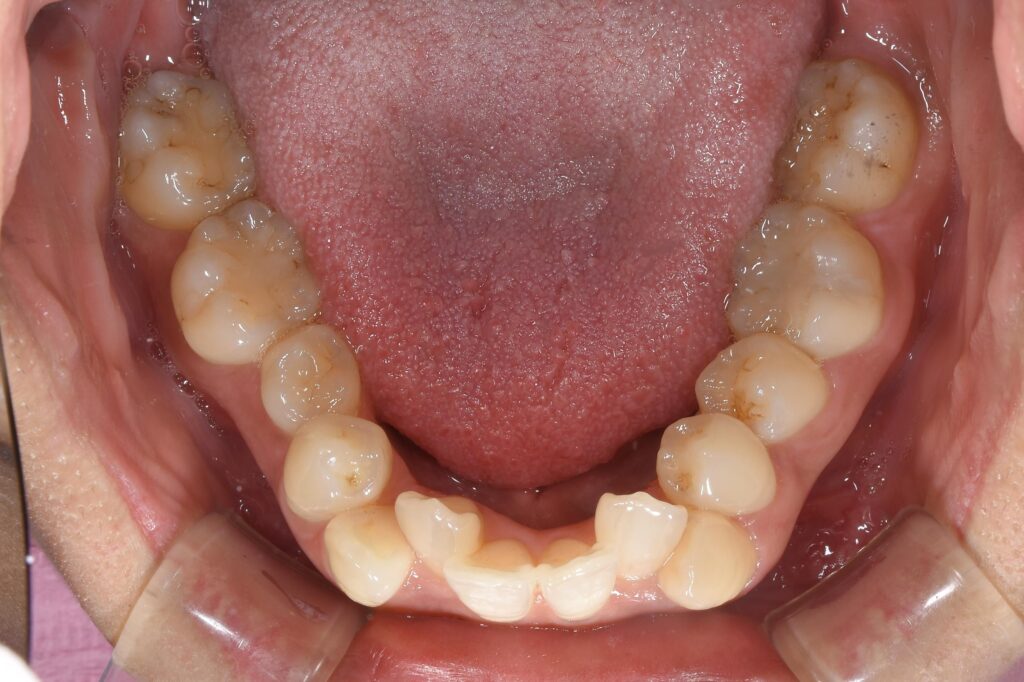

まずは術前の状態です。

【矯正開始前】

下顎の写真です。

以前の投稿でも記載しましたが、歯を並べるためには歯が並ぶスペースが必要です。初診時のこの状態を診察した時は、このように考えていました。

歯を並べるスペースが足りない、抜歯が必要だろう・・・